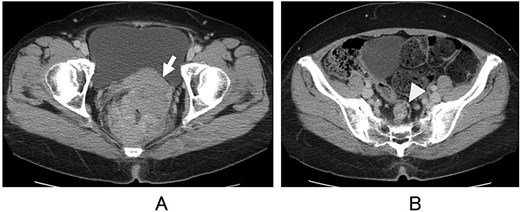

A 53-year-old woman presented with abdominal distension and hematochezia at a nearby hospital, where colonoscopy revealed a circumferential ulcerated tumour in the lower rectum. She was subsequently admitted to our hospital for further evaluation and treatment. Abdominal computed tomography showed localized wall thickening of the upper and lower rectum, measuring 75 × 72 × 95 mm, with uterine invasion (Fig. 1A) and two swollen regional lymph nodes (Fig. 1B). No distant metastases, including liver or lung metastasis, were detected. The proximal colon was distended due to stenosis, and a loop colostomy was created in the right transverse colon. The colonoscope could not pass beyond the tumour, and histologic examination of the endoscopic biopsy specimen confirmed tubular adenocarcinoma. Magnetic resonance imaging further clarified the uterine invasion and showed no evidence of lateral lymph node metastasis. Transvaginal examination by a gynecologist revealed no tumor invasion into the vaginal cavity.

Computed tomography. Direct invasion of the uterus (A, arrow) and regional lymph node metastasis (B, arrowhead) are shown.